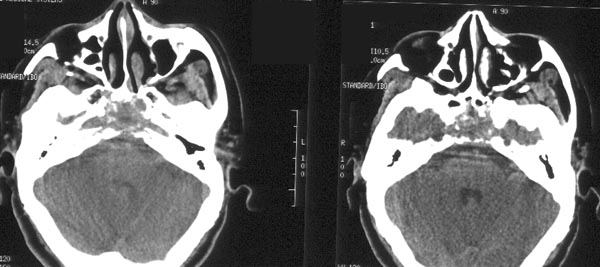

男性,48岁。吸涕带血2月余。

ct平扫:鼻咽腔明显狭窄,鼻咽顶壁、顶后壁、后壁、双侧壁增厚,右侧甚,右侧鼻咽旁间隙、颈动脉间隙见软组织肿物占据,肿物向前达后鼻孔,向下达右侧口咽,肿物向中颅窝侵犯致广泛颅底骨质破坏:包括枕骨斜坡、枕大孔、蝶窦、鞍底、双侧蝶骨大翼、双侧岩尖、双侧翼板。蝶窦、蝶鞍为软组织肿物占据,左侧海绵窦稍增厚。左侧鼻咽旁间隙、颈动脉间隙未见明显异常。

ct诊断:考虑鼻咽癌,并口咽受侵犯、颅底骨质破坏。